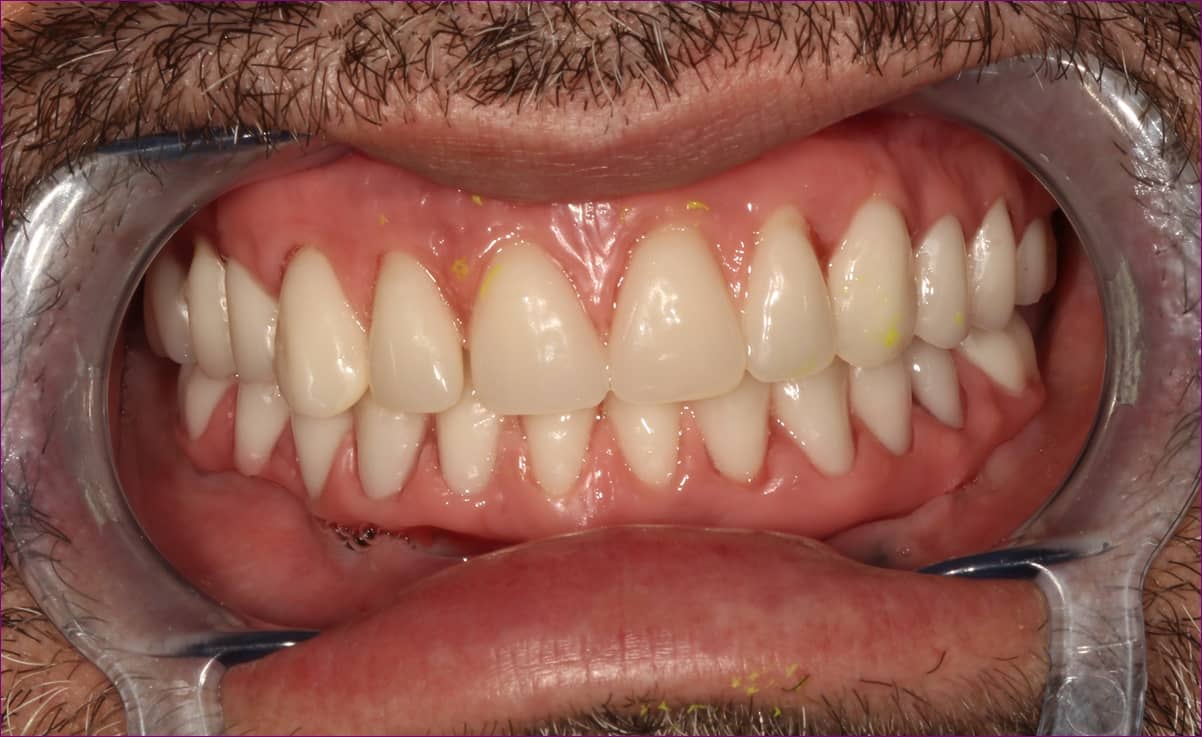

A mattpróba

A vázpróbát követően a fogtechnikai labor elkészítette a csavarozható hídpótlás vázának leplezését. A leplezés tulajdonképpen a külső megjelenést takarja, vagyis ilyenkor már szinte a kész pótlásról beszélhetünk. A mattpróba alkalmával becsavarozzuk, majd ellenőrizzük a szájban a pótlást. Ez a lépés már páciensünk számára is izgalmas, mivel a fogak, síkok kinézete, alakja már kontrollálható, ugyanakkor a módosítása még mindig lehetséges. Amennyiben mind a páciens, mind az orvos elégedett az eredménnyel, a fogtechnikai laborban a munkát készre égetik, a magas esztétikai végeredményt elérő módosításokat elvégzik.